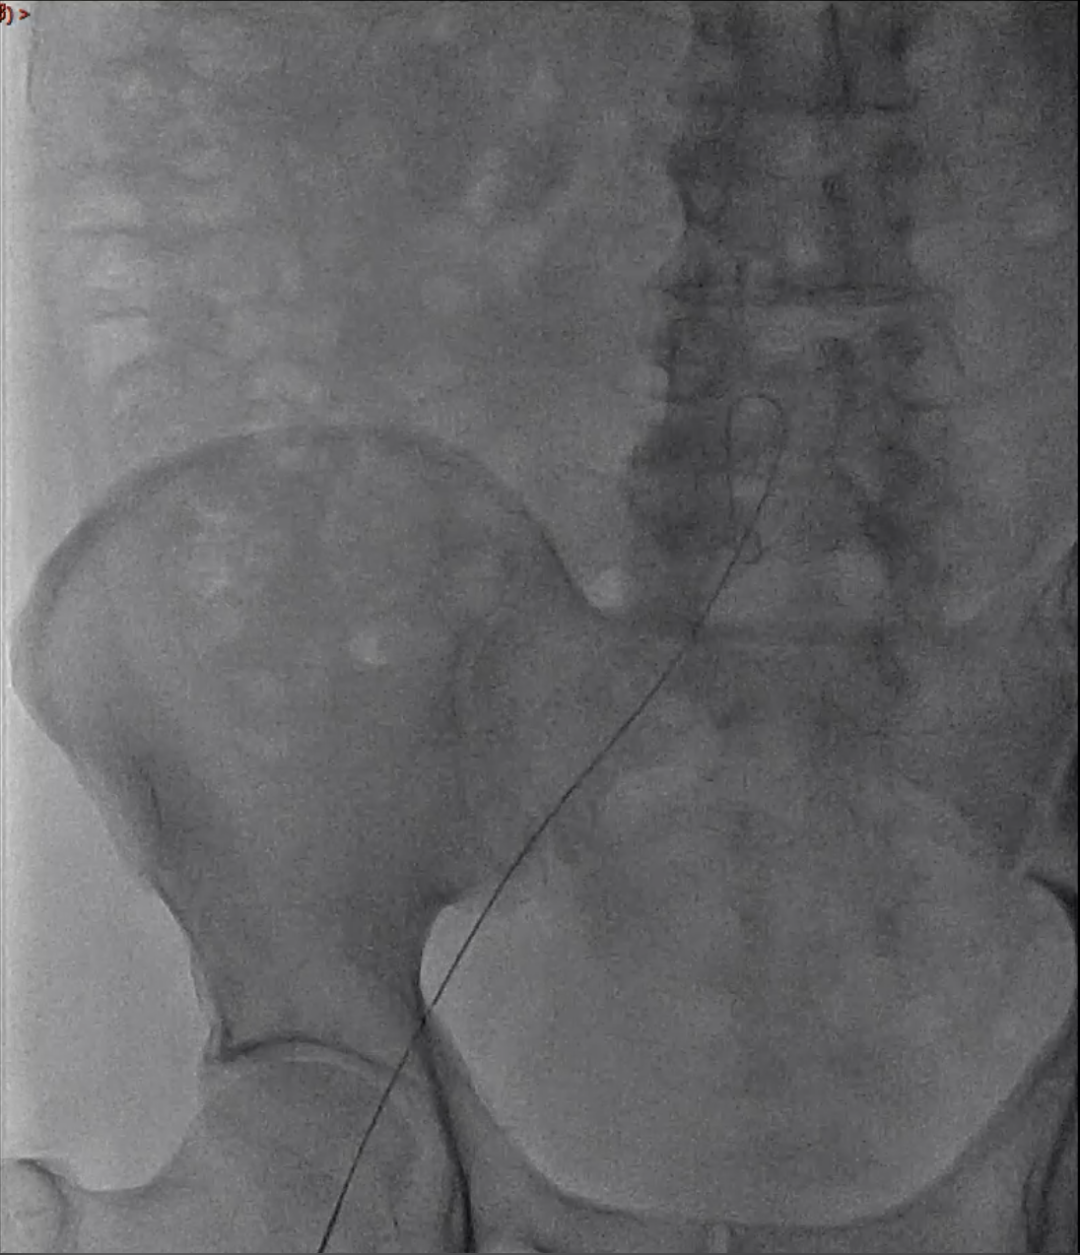

尝试经侧支逆行开通

使用微导管和导丝配合,尝试由股深动脉逆向开通。经尝试,逆向导丝(UB3)通过闭塞段,由于正向通道较小,未能与正向导丝进入同一微通道实现交汇。逆向微导管通过闭塞处困难。

经激光消蚀后,通过导丝导管配合,逆向导丝轻松通过闭塞段。

逆向导丝到达股浅动脉近段,进入正向套鞘,导丝体外化,建立轨道。